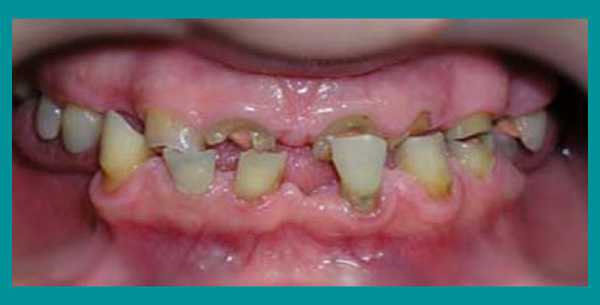

Пациент обратился с жалобами на истирание зубов верхней челюсти и, соответственно, снижение высоты верхних резцов до такой степени, что они перестали быть видны при улыбке. В результате клинического обследования челюстно-лицевой области не выявлено мышечно-фасциальных напряжений, движения нижней челюсти были в полном объеме, симметричные, патологических изменений со стороны ВНЧ сустава не выявлено. Прикус прямой (рис. 1) . На фронтальных зубах верхней челюсти 13—23 определяются окклюзионные фасетки истирания, клиновидные дефекты в области 24 и 25 зубов (рис. 1, 2). Высоту нижних зубов не планировалось изменять, хотя на них также имелись окклюзионные фасетки истирания, но с небольшой потерей тканей (рис. 3, 15) , поэтому прикус повышался без трансверсальных и сагиттальных перемещений нижней челюсти, а именно — в привычной окклюзии только за счет увеличения высоты верхних зубов.